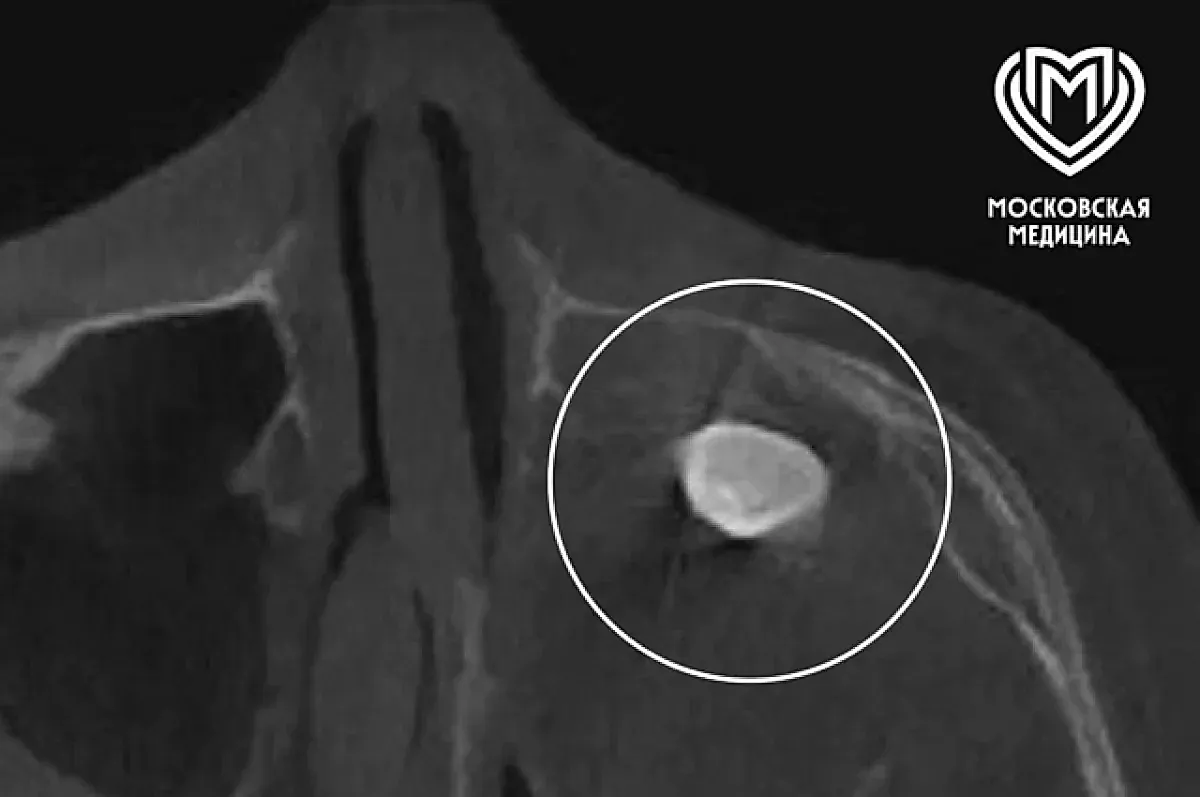

15-летний подросток, поступивший в клинику с жалобами на асимметрию лица и постоянную заложенность носа, стал героем необычной истории спасения. Родители, заметившие изменения внешности своего сына, обратились за профессиональной консультацией. В частной клинике при обследовании было выявлено наличие сформировавшегося зуба в гайморовой пазухе — области, расположенной в верхней части носа, вблизи глаз.

Во время хирургического вмешательства врачи обнаружили внутри носовой полости необычное образование, которое оказалось тератоматой — редким типом эмбрионального новообразования. Такой вид опухоли содержит элементы тканей, свойственные разным частям тела, что делает его уникальным в медицинской практике. В данном случае, тератома являлась доброкачественной и занимала почти всю левую часть носа, что и объясняло появление симптомов и не позволяло выявить новообразование на стандартных рентгенах и КТ (компьютерной компьютерной томографии).